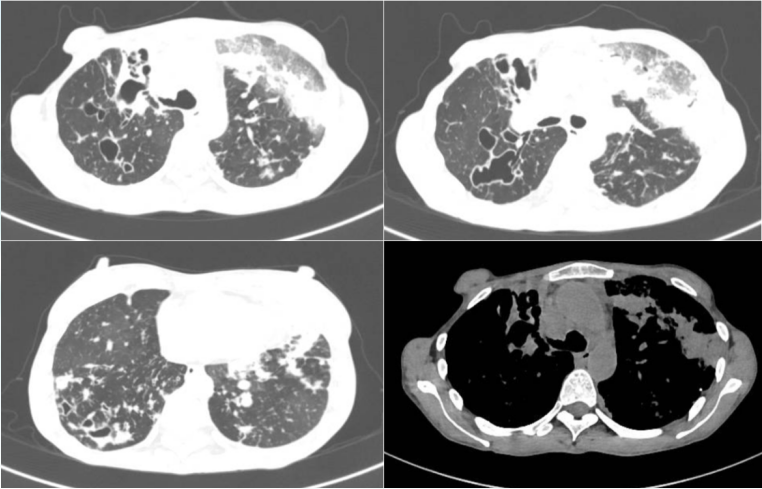

10月11日至10月18日胸片可见,患者肺门周围渗出影有所吸收。10月18日胸片提示左上肺有不张表现(图9)

图片

9  患者病程中胸片变化

10月21日复查胸部+全腹部CT:右上肺支扩伴感染病灶较刚入院时明显增多,左上肺病灶较前吸收;下肺渗出性病灶,包括右中叶、左上舌段、右下叶基底段实变增多;腹腔有不全性肠梗阻表现。

10月28日脱机拔管, 复查胸片: 双肺渗出和实变影、双侧胸腔积液较前明显吸收(图10)